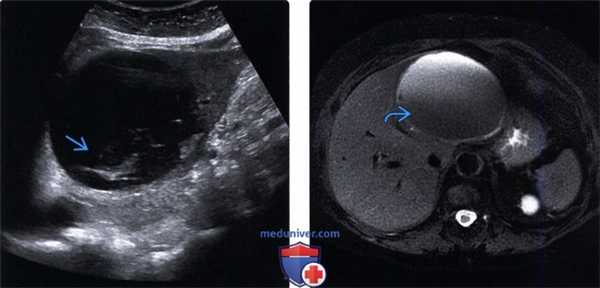

Клиническое наблюдение. Пациент П., 65 лет, обратился на консультацию в клинику факультетской хирургии им. И.И. Грекова СЗГМУ им. И.И. Мечникова 23.05.17 с диагнозом «киста холедоха» (общего желчного протока — ОЖП). Из анамнеза известно, что пациент считает себя больным около года, когда отметил появление чувства распирания и тяжести в верхних отделах живота, больше справа. Появление подобных жалоб ни с чем не связывает. Самостоятельно не лечился, за медицинской помощью не обращался. Ухудшение самочувствия отметил в конце апреля 2017 г., когда появились выраженные боли в правом подреберье, в связи с чем обратился в поликлинику. В амбулаторном порядке было выполнено УЗИ органов брюшной полости (рис. 1), при котором выявлено жидкостное образование в проекции ворот печени, которое было трактовано как киста ОЖП и рекомендована консультация хирурга-гепатолога.

Рис. 1. УЗ-скан образования брюшной полости.

После консультации специалистами клиники в амбулаторном порядке выполнен ряд исследований. При спиральной компьютерной томографии органов брюшной полости обнаружены признаки кистозного образования в области ворот печени (более вероятно киста ОЖП) от 11.05.17 (рис. 2). Ввиду неоднозначности трактовки 30.05.17 выполнена магнитно-резонансная томография в режиме холангиографии, при которой визуализировалась киста брюшной полости размерами 66×44×48 мм с локализацией в области ворот печени, оттесняющая желчный пузырь кнаружи. Образование прилежало к нижней поверхности печени, к передним отделам и сосудистой ножке правой почки, нижней полой вене, к общему печеночному протоку без сужения их просвета, к головке поджелудочной железы и к стенке двенадцатиперстной кишки (ДПК).

Рис. 2. Данные спиральной компьютерной томографии органов брюшной полости с внутривенным контрастированием.

Следует отметить, что после введения гепатотропного парамагнитного контрастного вещества накопление его в сосудистой фазе сканирования не определялось.